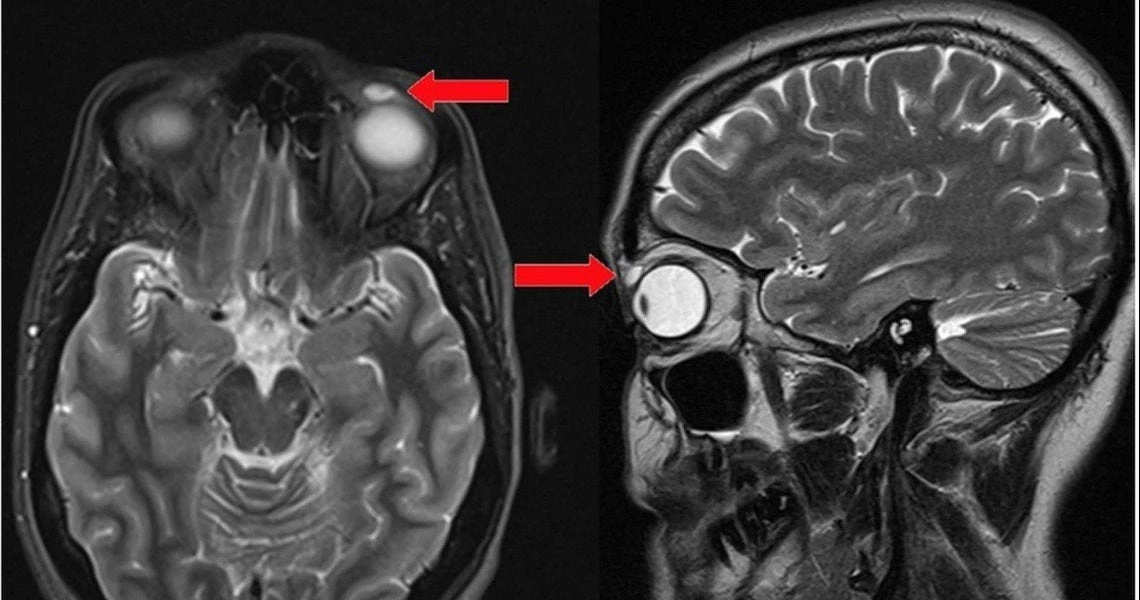

Γυναίκα βρήκε τον φακό επαφής της κρυμμένο στο βλέφαρο μετά από 28 χρόνια!

Πριν από περίπου τρεις δεκαετίες, ένα 14χρονο κορίτσι στην Αγγλία χτύπησε το μάτι της σε έναν αγώνα αντιπτέρισης και έχασε τους φακούς επαφής της. Θα σκεφτείτε, σιγά το πράγμα. Τι θα λέγ...